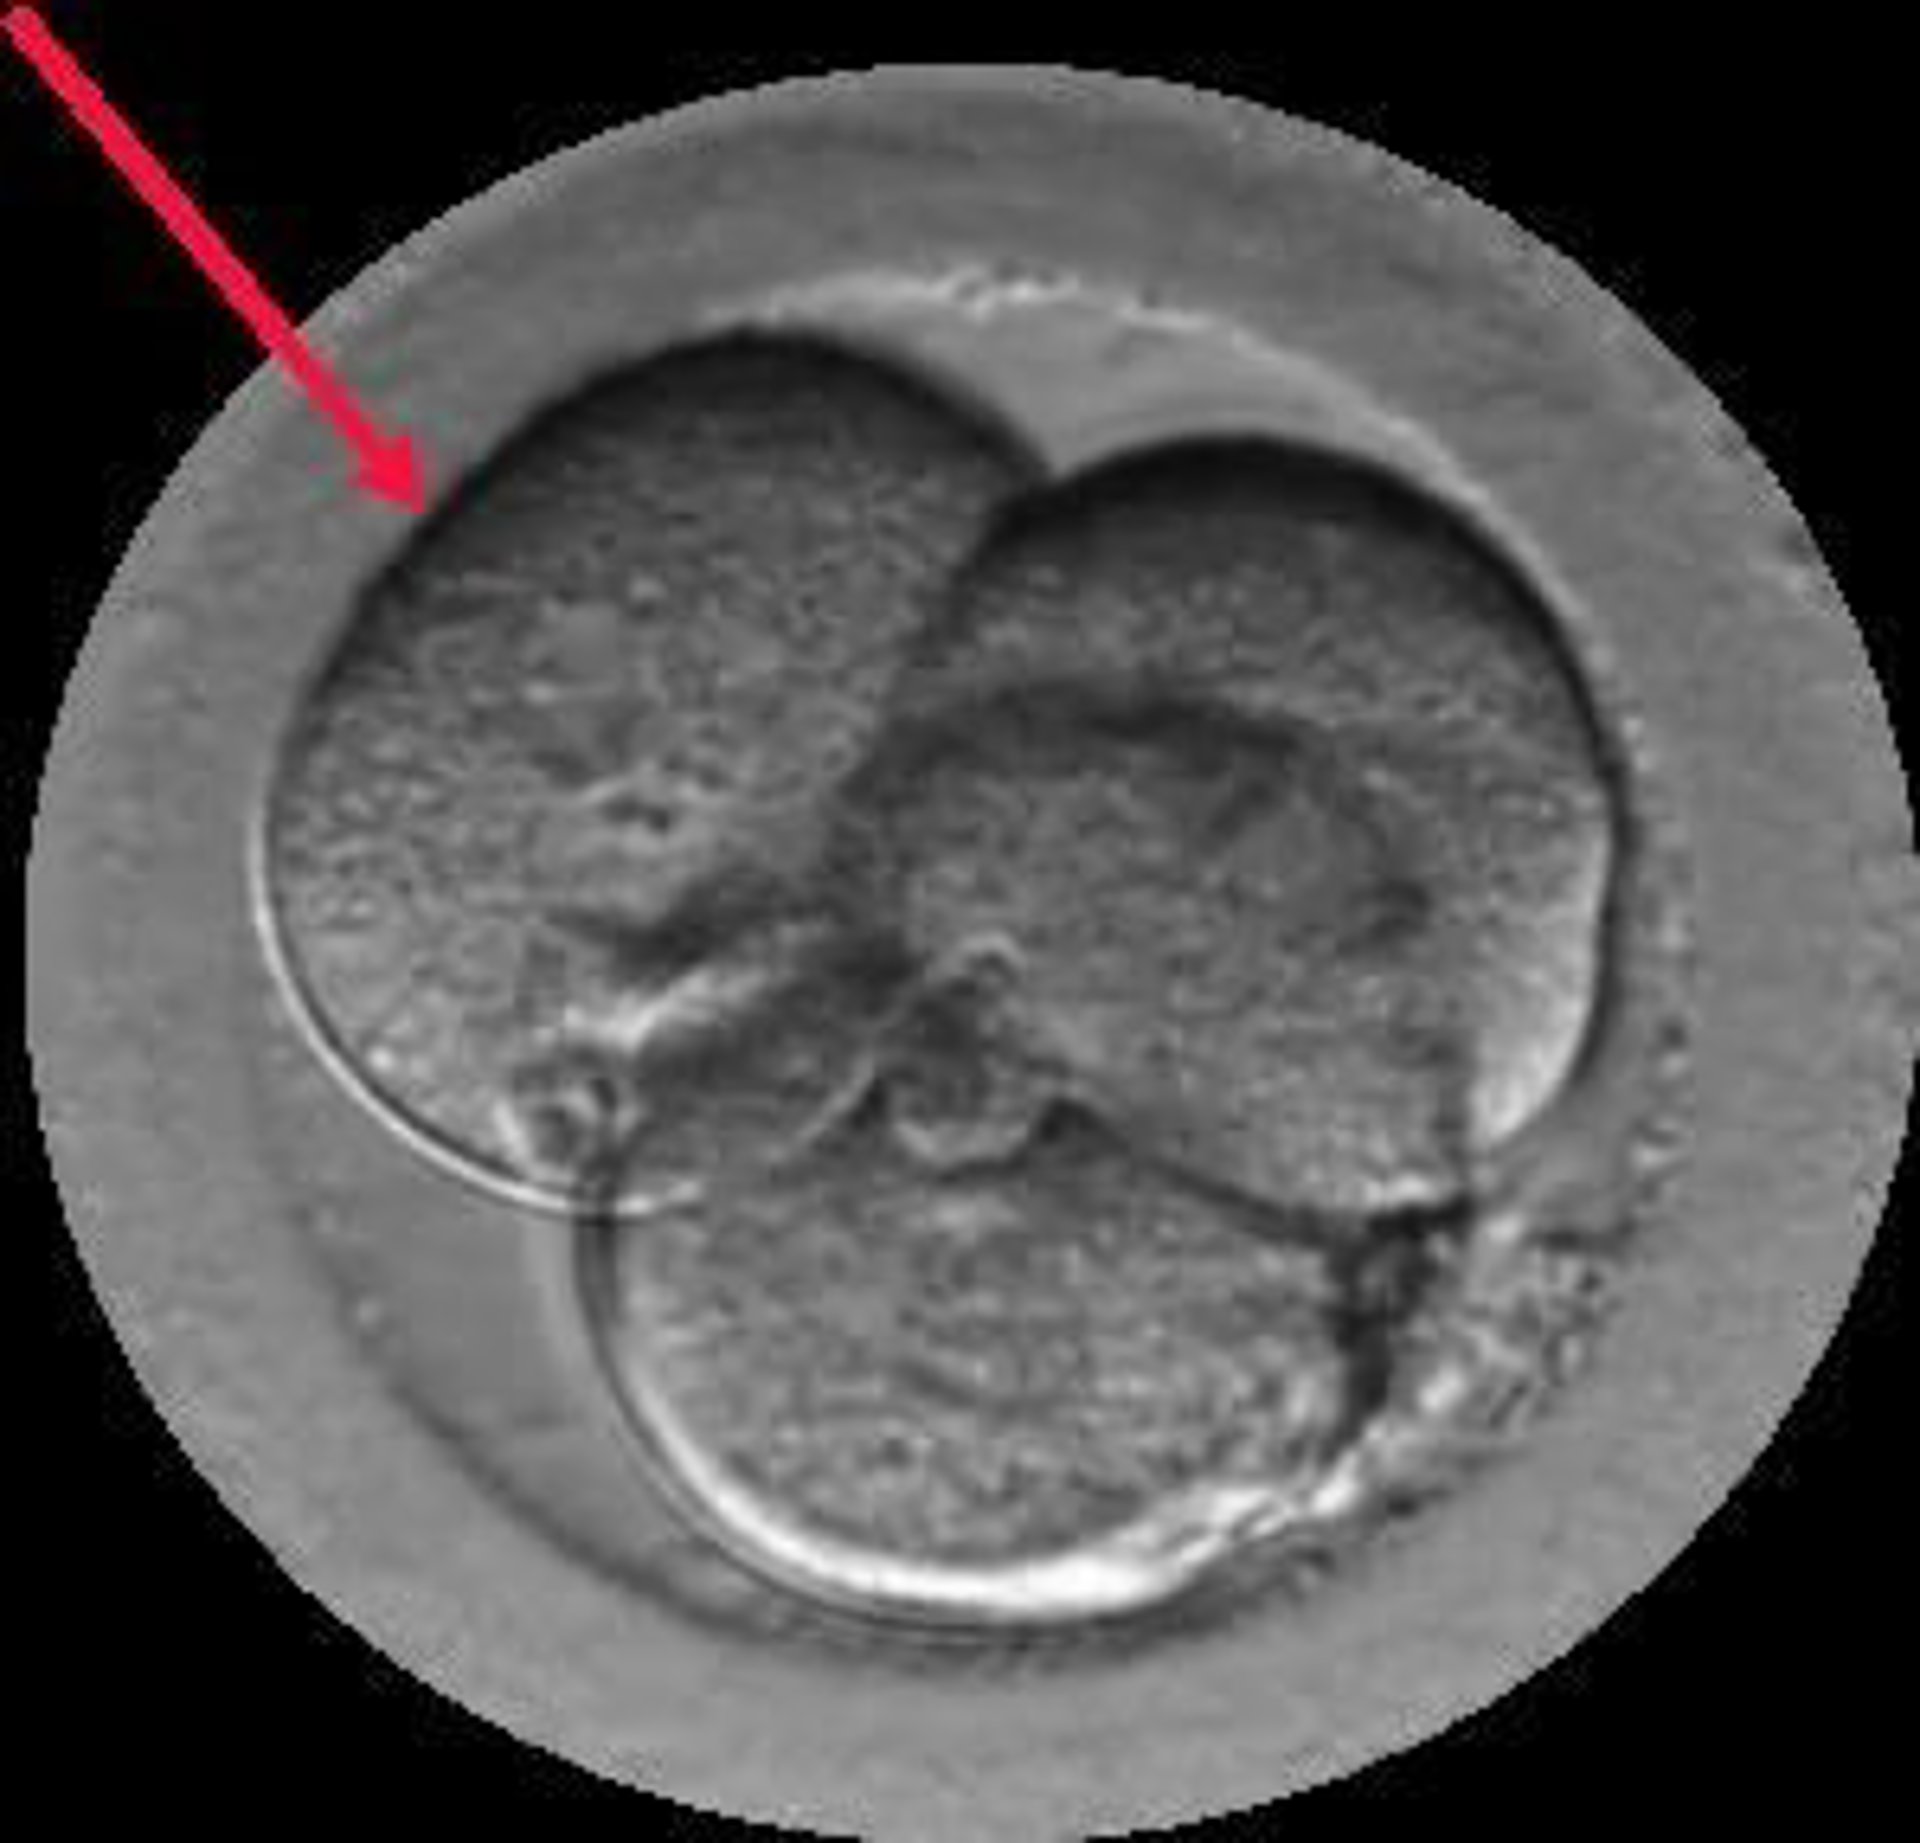

Embrión Multinucleado.

Embrión Multinucleado. - Institut Marqus

El Dr. Borja Marqus es el autor del estudio Signos de auto-reparación de los embriones en el laboratorio de FIV cuyas conclusiones apuntan que los embriones poseen un mecanismo de auto-corrección ignorado hasta hoy. Según este trabajo que se presenta esta semana en Murcia, en el 36 Congreso de la Sociedad Española de Ginecología (SEGO), embriones que han sufrido división reversa (desaparición de alguna de sus células) o multinucleación (presencia de dos o más núcleos en alguna de sus células) pueden acabar con éxito, es decir, con un embarazo normal y el nacimiento de un bebé sano.

Gracias a los incubadores con cámaras time-lapse (Embryoscope), en los laboratorios de Institut Marqus ha sido posible captar las imágenes de embriones con división reversa reabsorbiendo sus propias células y de embriones multinucleados expulsando las células anómalas en el 4 o 5 día de vida. Para conseguirlo, se ha analizado el desarrollo de 21.274 embriones, desde su fecundación hasta que llegaron a blastocisto.